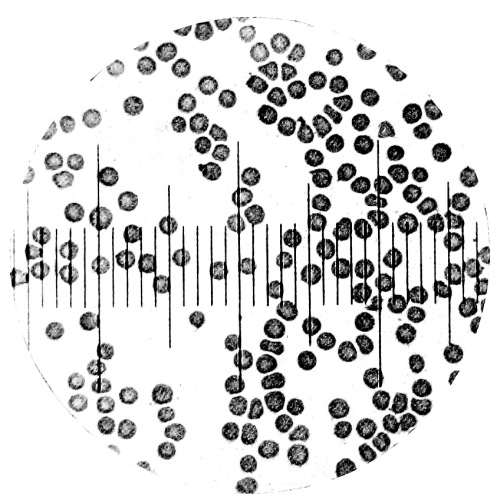

| 9. | Measurement of Blood Corpuscles (sheep) | 97 |

| 10. | Photo-micrograph of Red Blood Corpuscles from Domestic Fowl | 99 |